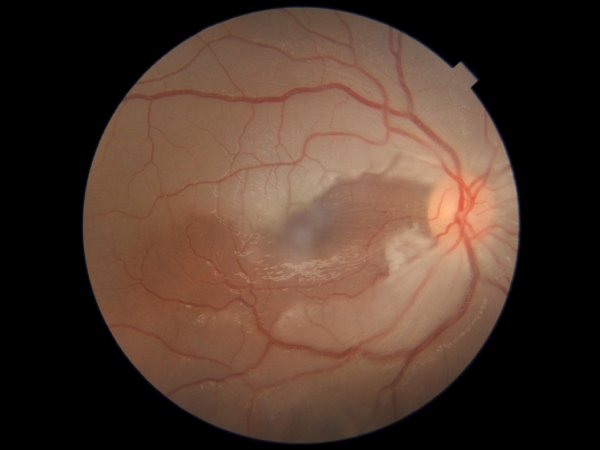

Branch retinal vein occlusion with collaterals and macular edema

BRVO post sectorial laser photocoagulation